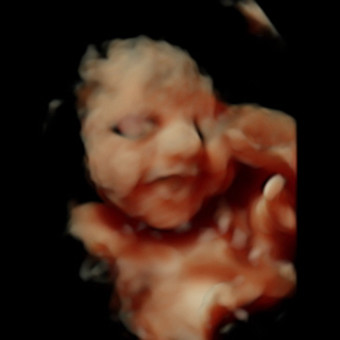

Come celebrate our sweet little Girl with us